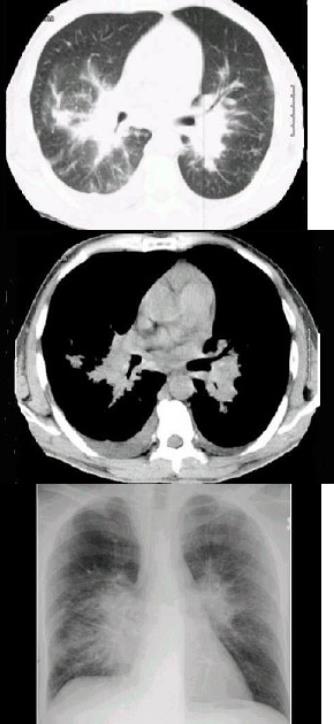

- 单项选择题2、 男,66岁,胸痛1个月,胸部CT如图,最可能的诊断是()。

A、右下肺周围型肺癌

B、右下肺动静脉瘘

C、右下肺肉瘤

D、右下肺错构瘤

E、右侧炎性假瘤